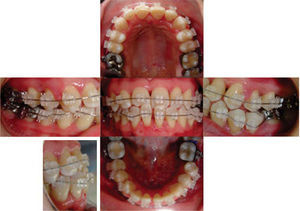

TREATMENT PROGRESSTreatment was begun with the placement of fixed appliances, 0.022” slot Roth system, in the upper arch. The Department of Periodontics conducted the scaling and root planning in the lower anterior area and subsequently, placed a free gingival graft. A month later fixed appliances were placed in the lower dental arch thus beginning the leveling and alignment with the corresponding archwires (Figure 6). Three segments were formed throughout this phase: one anterior segment and two posterior ones. After the segments were formed a single keyhole loop (SKL) archwire was placed in the lower arch maintaining a segment with ligature wire from lower first molar to canine on both sides. The archwire was activated in the following appointment with a Suzuki retroligature to begin space closure (Figure 7A).

Once the spaces were closed, the archwire was tied with ligature wire to form a block of teeth from second premolar to second premolar on the upper and lower arch and began to use 3.5oz, 5/16” class III elastics with a vertical vector (Figure 7B). Subsequently, the teeth # 11 and 21 were rebuilt with composite to recover their form and aesthetics as well as to maintain what had been achieved.

A panoramic radiograph was obtained to reposition the brackets accordingly. The brackets form teeth #42 and 35 were repositioned to achieve root parallelism.

After bracket repositioning, a space opened between the lower right lateral incisor and canine and reseated so the SKL archwire was placed again to close that space (Figure 7C); four months after, the fixed appliances were removed (Figure 8). As retention a circumferential retainer was placed in the upper arch, while a fixed retainer made with a 0.0175” braided wire and bonded with fluid resin was placed in the lower (Figure 9).